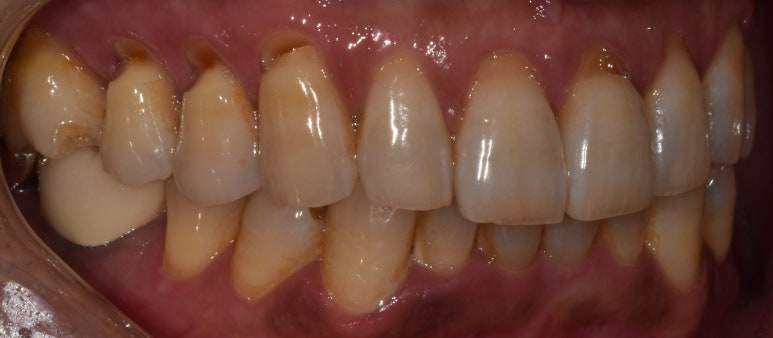

치경부마모증 실제 사례

53세 남성

촬영일자: 2022-09-30

위 사진은 치경부마모증이 심해진 환자분의 실제 사진인데요.

사진상으로 왼쪽 위 치아쪽(실제로는 오른쪽 위) 치경부 부분이 노출되고 패인 모습이 보이시죠?

아마 사진의 환자분께선 시린 증상을 많이 느끼셨을거예요.